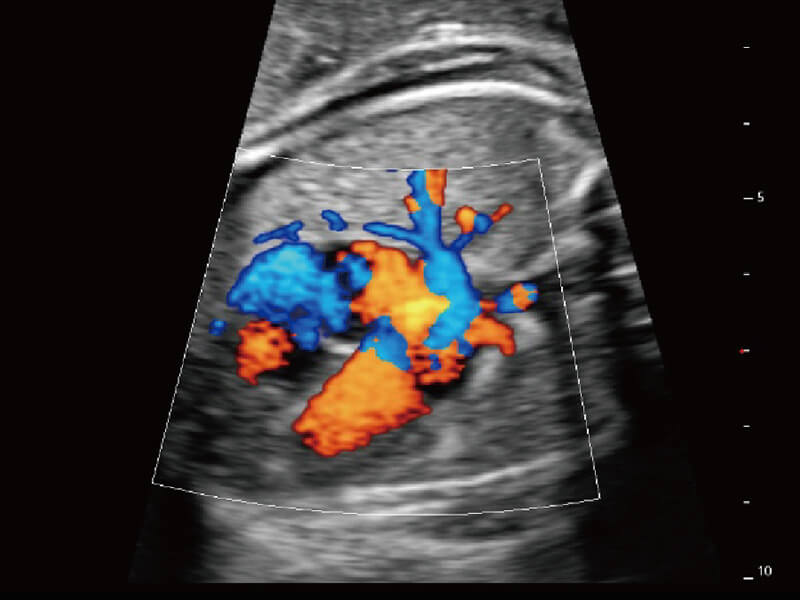

S60探头工艺,从前端信号处理每一个环节采集无损声学数据,真实还原组织原貌,再现解剖细节。